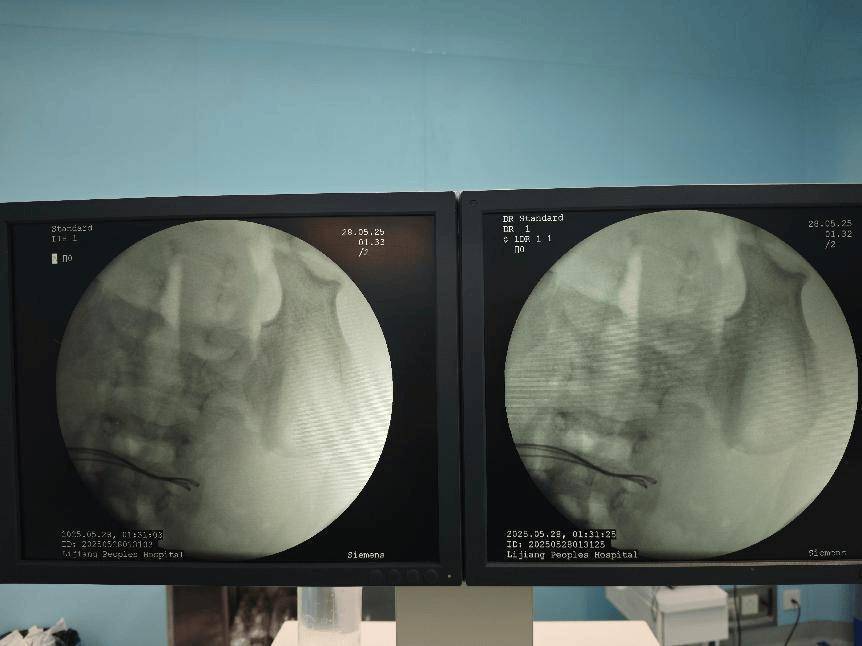

术前腹部DR片

术中完善床旁DR见腹腔内已无异物